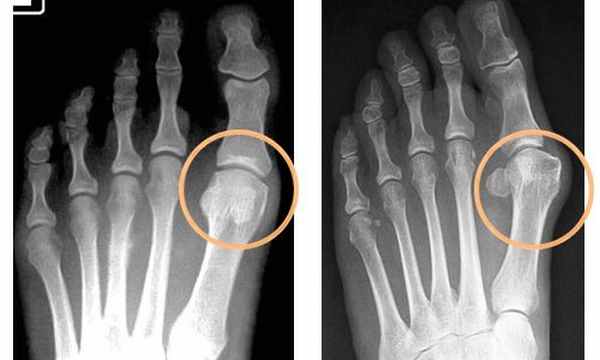

Рис. 2. Рентгенограмма правой стопы. По внутреннему краю расположена большеберцовая или медиальная сесамовидная кость, по наружному краю – малоберцовая или латеральная сесамовидная кость

Перелом сесамовидных костей происходит под действием большой силы. Повреждению сесамовидных костей способствуют эквинусная установка стопы, чрезмерные усилия, вызванные внезапным изгибом вверх большого пальца ноги, или спотыканием с ударом пальцами стопы об твердый предмет. При переломе может произойти как полная фрагментация сесамовидной кости, так и изолированное повреждение её суставной поверхности. Травма медиальной сесамовидной кости, которая расположена под выпуклой частью головки первой плюсневой кости, происходит чаще, чем травма латеральной кости. Перелом сесамовидной кости может быть как острым, так и усталостным. Острый перелом вызван травмой в виде прямого удара по подошвенной поверхности стопы. Острый перелом сопровождается болью. После травмы в месте перелома имеется отек, гематома, локальная болезненность. Пациент жалуется на невозможность полноценно нагружать передний отдел стопы. Травма сесамовидных костей чаще носит хронический характер в результате многократной, повторяющейся нагрузки на передний отдел стопы, которая сопровождается разгибанием пальцев ноги. Хроническая травма приводит к усталостному стрессовому перелому, при котором имеется отек или припухлость мягких тканей. Усталостный перелом сесамовидной кости вызывает боль в основании большого пальца. Болевой синдром имеет длительный характер, возникает при разгибании пальца, усиливается при росте физической активности и уменьшается после отдыха. При болях есть снижение силы отталкивания в 1 плюсне-фаланговом суставе, что уменьшает эффективность ходьбы, особенно у лиц, которые носят обувь на высоком каблуке долгое время. Перелом сесамовидной кости трудно обнаружить на рентгеновском снимке, в связи с чем для диагностики прибегают к сканированию костей или МРТ. Хроническая травма приводит к сесамоидиту, который проявляется в виде периодически обостряющегося воспаления и болевого синдрома на месте бывшей когда-то травмы. Вялотекущее, хроническое воспаление захватывает сесамовидные кости и сухожилия, связанные с этими костями. Сесамоидит обостряется под действием повышенного давления на подошвенную поверхность стопы. Сесамоидит дает тупую боль под суставом большого пальца, которая зависит от обуви. Узкая, тесная обувь или жесткая подошва способствуют росту дискомфорта в ногах.

Перелом сесамовидной кости. Нужно помнить, что иногда выявляется «дольчатая» сесамовидная кость. Обычно состоящая из двух (бывает больше) элементов. Но в таком случае на рентгенограмме видны ровные и гладкие края «долек»